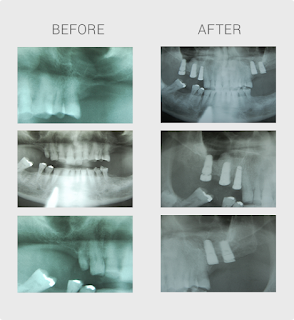

replace the old tooth. Dental implants are similar to having new set of teeth without

the natural process of growing. Instead, a dental procedure is done to install

a natural looking set of artificial teeth. Unlike dentures, a dental implant is

attached in the bone like a real tooth. This keeps the dental implant stable

and fix within your gums all the time.